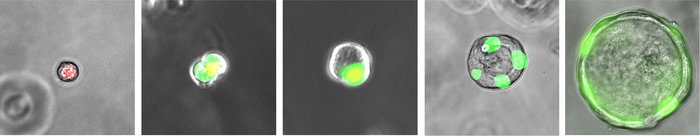

图:人类ES细胞衍生的RASC(呼吸气道分泌细胞,在培养过程中逐渐转化为肺泡2型细胞)

研究人员今天在《自然》杂志上报道了他们的发现,他们分析了人类的肺组织,识别新的细胞,他们称之为呼吸道分泌细胞(RASCs)。这些细胞排列在肺深处的微小气道分支上,靠近氧气交换为二氧化碳的肺泡结构。科学家们发现rasc具有类似干细胞的特性,使其能够再生对肺泡正常功能至关重要的其他细胞。他们还发现,吸烟和与吸烟有关的常见疾病——慢性阻塞性肺病(COPD)会破坏rascs的再生功能——这表明纠正这种破坏可能是治疗COPD的一种好方法。

通过观察RASCs和肺泡中一个重要的祖细胞AT2细胞之间的基因活动相似性,该团队有了进一步的发现:RASCs,除了其分泌功能外,还充当AT2细胞的前身——使AT2细胞再生以维持AT2细胞的数量,并保持肺泡的健康。